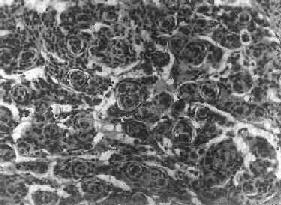

肉眼观,瘤组织呈鱼肉状,色灰红。镜下,肿瘤由圆形、椭圆形或胡萝卜形细胞构成,胞核着色深,胞浆少而边界不清楚,有多少不等的核分裂像。细胞密集,间质中有纤细的纤维,血管不多。瘤细胞环绕一个嗜银性纤细的神经纤维中心作放射状排列形成典型的菊形团(图16-26),这对髓母细胞瘤的病理诊断有一定的意义。瘤细胞具有向神经元及神经胶质双向分化的潜能,既能向神经母细胞、节神经细胞分化,也能向胶质母细胞、星形胶质细胞分化。如瘤细胞侵入软脑膜,可在蛛网膜下腔脑脊液中广泛播散转移。

图16-26 髓母细胞瘤

瘤细胞较小,着色深,密集排列,有菊形团形成